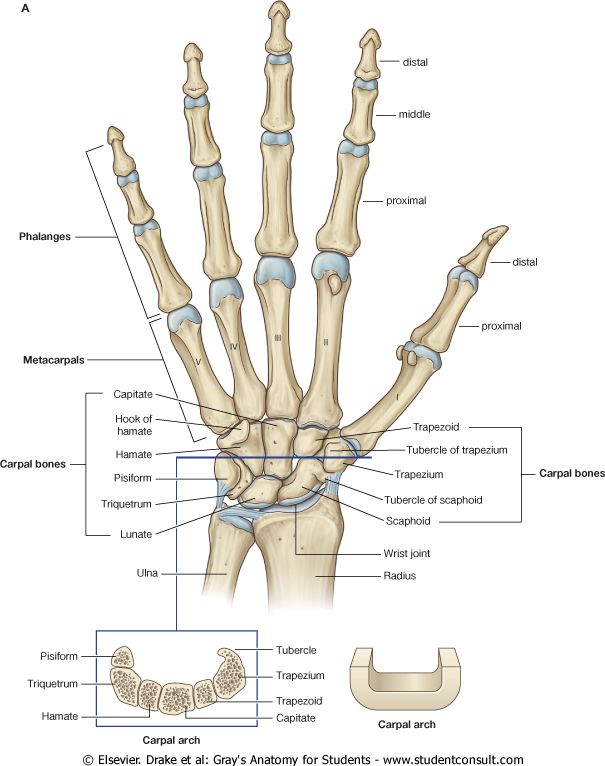

读手骨:从手掌和手腕评估骨龄

骨骼成熟度主要是通过骨骺中次级骨化中心的发育和骨化程度来评估的。几十年来,评估骨骼成熟度通常是根据对手骨和手腕的骨骼发育情况进行可视化评估来进行的。以下是放射科医生在查看手部 X 光片时看到的内容:

现在评估骨龄的两种最常用的技术是 Greulich-Pyle 法和 Tanner-Whitehouse(TW2)法。这两种方法都是根据成熟度指标,用左手手掌和手腕的放射图像评估骨骼成熟度,即管状骨的骨骺从骨化的最早阶段到它们和骨干融合的过程中放射影像呈现出的变化,或者是扁骨在变成成年人骨骼形状之前在放射影像上呈现出来的变化……别担心,我们在此之前也没听过这些。我们将这一过程展示在下图中: